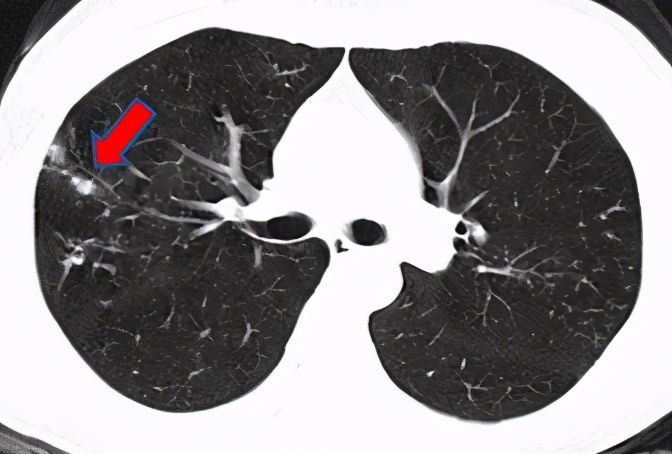

医生安排赵阿姨做支气管镜检查,病理初步排除了肿瘤的可能;又进一步做了国际上最先进的“微生物基因检测”(NGS),确诊赵阿姨为胞内分枝杆菌感染。医生说,这个菌是结核菌的兄弟、是“非结核分枝杆菌”大家族中的一员,没有传染性;治疗时间虽然比较长,但是可以防止肺功能变差,减少对寿命的影响。这下结节病因明确了,赵阿姨心中一块石头落了地。经过细致的治疗,赵阿姨现症状明显好转,重新投入到了带孙辈的“甜蜜的负担”之中。